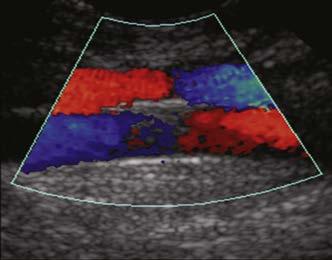

enable color-coded 2D and 3D presentations of Doppler information (color-Doppler displays) to be superimposed on gray-scale anatomic images (Figure 1-13). Doppler information is applied to loudspeakers for audible evaluation and to spectral-Doppler displays for quantitative analysis (Figure 1-14). The spectral-Doppler operation includes

FIGURE 1-13 Color-Doppler displays of blood flow. Presented in forms called (A) colorDoppler shift, (B) color-Doppler power, and (C) three-dimensional color-Doppler power displays.